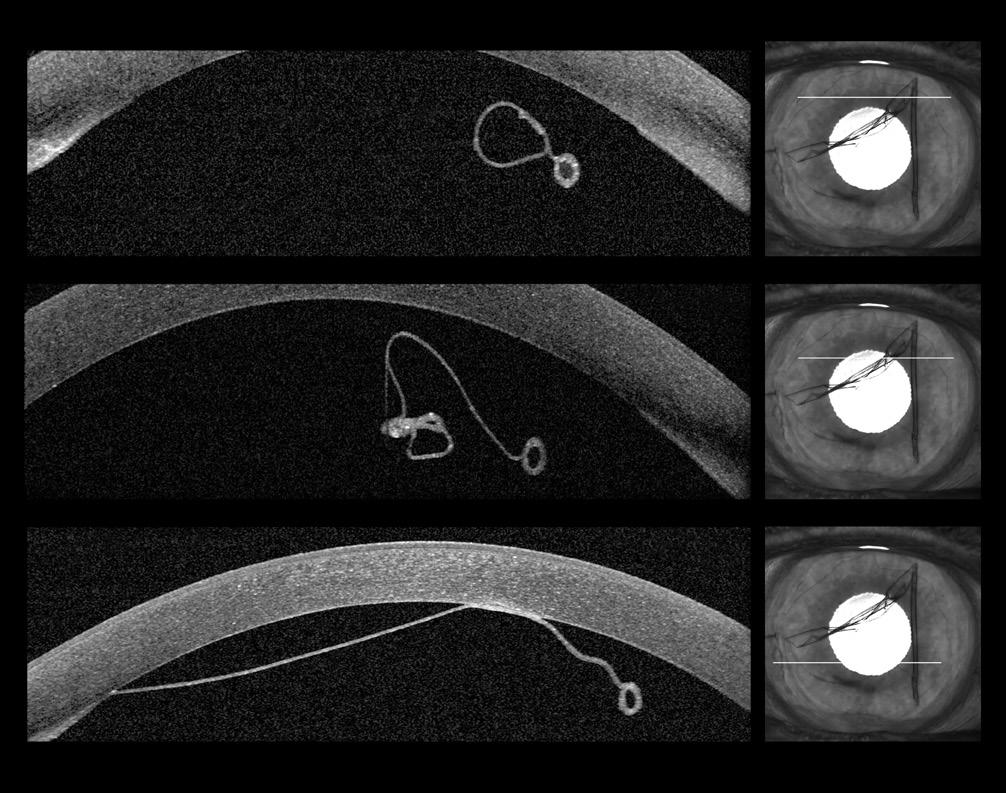

Snake Spectacle Vessel Permeability to Sodium Fluorescein

Keywords

Python regius; ball python; ecdysis; fluorescein angiography; permeability; snake spectacle.

Objective

Assess vascular permeability of the snake spectacle to sodium fluorescein during resting and shedding phases of the ecdysis cycle.

Animal Studied

Ball python (Python regius).

Procedures

The snake was anesthetized, and spectral domain optic coherence tomography was performed prior to angiographic procedures. An electronically controlled digital single-lens reflex camera with a dual-head flash equipped with filters suitable for fluorescein angiography was used to make images. Sodium fluorescein (10%) solution was administered by intracardiac injection. Angiographic images were made as fluorescein traversed the vasculature of the iris and spectacle. Individually acquired photographic frames were assessed and sequenced into pseudo video image streams for further evaluation.

Conclusions

Fluorescein angiograms of the snake spectacle were readily obtained. Vascular permeability varied with the phase of ecdysis. Copious leakage of fluorescein occurred during the shedding phase. This angiographic method may provide diverse opportunities to investigate vascular aspects of snake spectacle ecdysis, dysecdysis, and the integument in general.